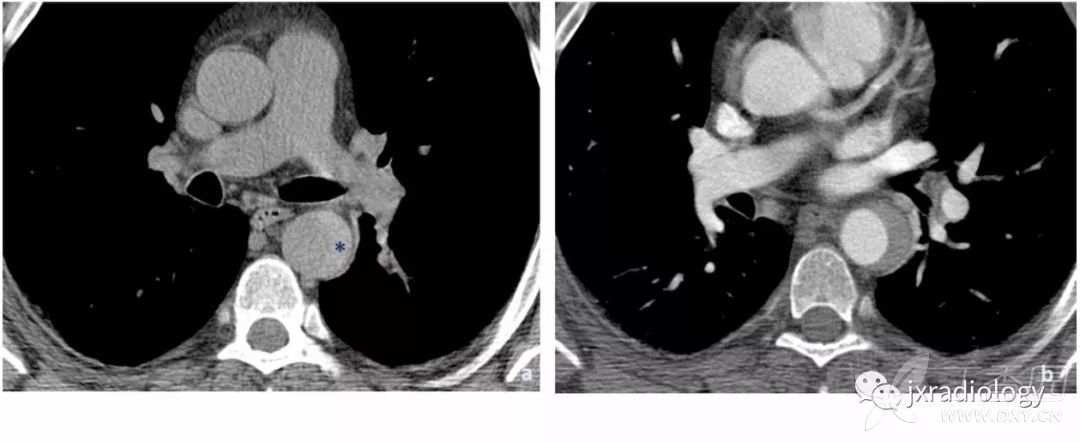

平扫CT上显示广泛的动脉粥样硬化通常是PAU患者的一个特征。注射对比剂后,主动脉壁出现不规则边缘和围绕溃疡基底部的内膜钙化提示PAU诊断( 图13 )。

图13:在轴位非增强CT显示主动脉后壁广泛的动脉粥样硬化(a图中箭头)。注射对比剂后,没有内膜瓣的情况下主动脉的后囊袋状突起(b和c图的星号)。

当发生破裂时,很难区分破裂的是动脉瘤或复杂的动脉粥样硬化性溃疡。在这两种情况下,都需要立即进行手术治疗。非穿透性溃疡一般限于内膜并常常无症状( 图14 )。

图14:非穿透性溃疡的患者。

血栓伴局灶性溃疡(a和b图的箭头),但没有对比剂超出内膜,也不存在壁内血肿。病人无症状。